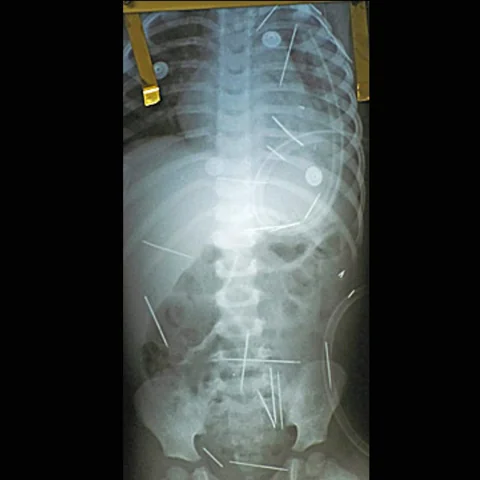

40 إبرة في طفل جراء طقس من السحر الأسود